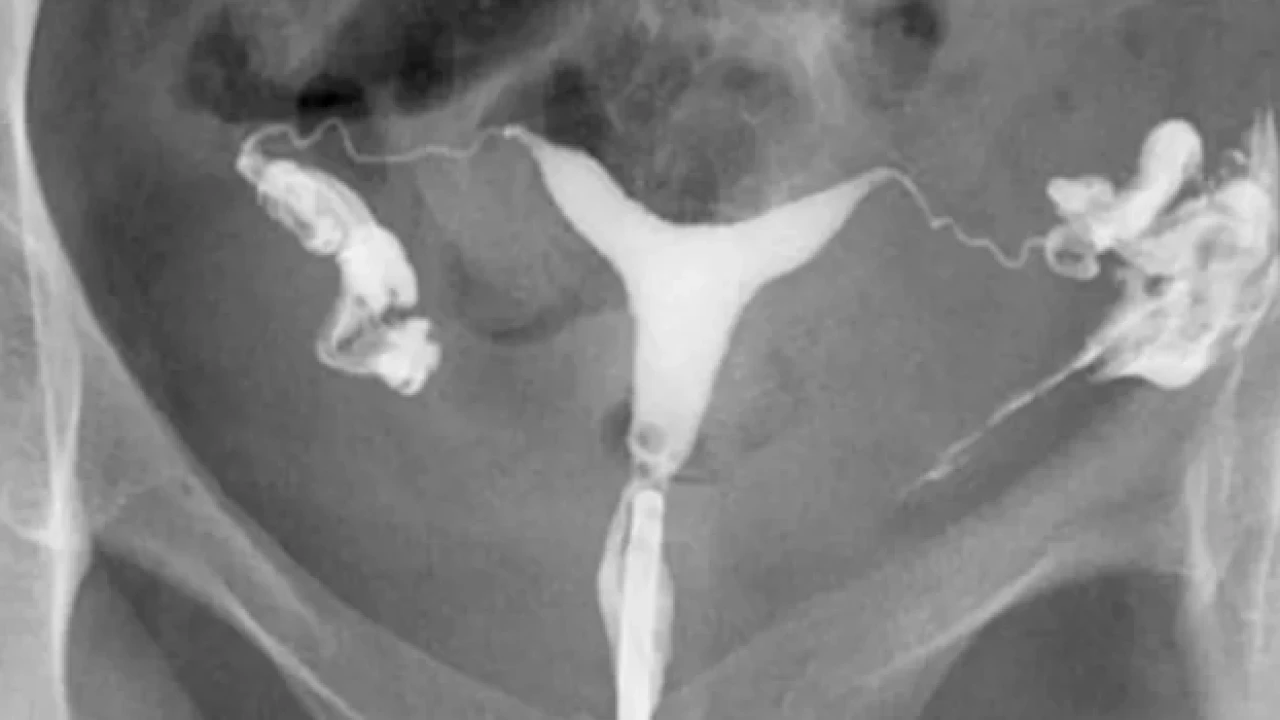

Rahim filmi, tıbbi ismiyle histerosalpingografi (HSG), rahim ve fallop tüplerinin radyolojik olarak görüntülendiği bir tetkiktir. Bu işlem sırasında rahime özel bir boyar madde enjekte edilir ve X-ışını yardımıyla bu bölgelerin görüntüsü alınır. Rahim filmi, kadınların üreme sağlığını değerlendirmek amacıyla özellikle kısırlık soruşturmalarında ve tüp yollarının açıklığını kontrol etmek için kullanılır.

Rahim filmi, kadınların üreme sağlığıyla ilgili sorunları değerlendirmek amacıyla çektirilir. Özellikle kısırlık sorunları, tüp tıkanıklığı ya da rahimdeki potansiyel şekil bozuklukları gibi durumların teşhisinde etkili bir yöntemdir. Aynı zamanda tekrar eden düşüklerin nedenini araştırmak veya pelvik ağrının kaynağını belirlemek için de doktorlar tarafından önerilebilir.